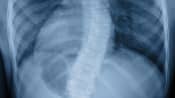

X-ray scan showing spine curvature caused by scoliosis

Scoliosis Symptoms